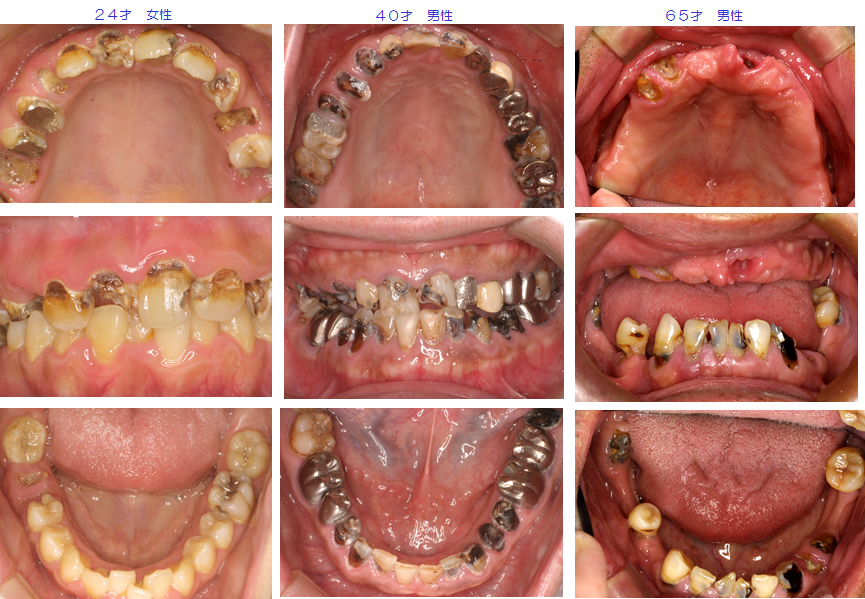

むし歯を放置した結果、破壊された口腔内